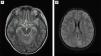

Dada la mala evolución, se solicita resonancia magnética (RM) con (fig. 1A) signos de meningitis infratentorial (fig. 1B), ventriculitis generalizada y encefalitis isquémica supratentorial. Tras mejoría clínica, se procede a la extubación a los 5 días y se objetiva paraparesia flácida arrefléxica con hipoestesia y síndrome de cola de caballo. La RM medular compatible con mielitis transversa1 (fig. 2A) y presencia de material purulento en fondo de saco dural con radiculitis2 y aracnoiditis de la cola de caballo (fig. 2B).